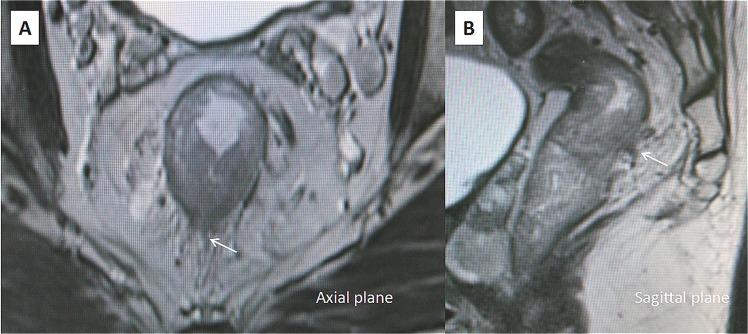

The purpose of this study was to evaluate the prognostic significance of the magnetic resonance imaging-detected extramural venous invasion (MR-EMVI), the depth of mesorectal extension (MR-DME), and lymph node status (MR-LN) in clinical T3 mid-low rectal cancer. One hundred and forty-six patients with clinical T3 mid-low rectal cancer underwent curative surgery were identified. Pretreatment high-resolution MRI was independently reviewed by two experienced radiologists to evaluate MR-EMVI score (0-4), MR-DME (≤4 mm or >4 mm), and MR-LN (positive or negative). The Cox-multivariate regression analysis revealed that the MR-EMVI was the only independent prognostic factor that correlated with overall 3-year disease-free survival (DFS) (p = 0.01). The survival analysis showed that patients with positive MR-EMVI, MR-DME > 4 mm, and positive MR-LN had a poorer prognosis in the overall 3-year DFS (HR 3.557, 95% CI 2.028 to 13.32, p < 0.01; HR 3.744, 95% CI:1.165 to 5.992, p = 0.002; HR 2.946, 95% CI: 1.386 to 6.699, p < 0.01). By combining MR-EMVI with MR-DME or MR-LN, the prognostic significance was more remarkable. Our study suggested that the MR-EMVI, MR-DME, and MR-LN were the important prognostic factors for patients with clinical T3 mid-low rectal cancer and the MR-EMVI was an independent prognostic factor.

本研究旨在评估磁共振成像检测到的外膜静脉侵犯(MR-EMVI)、直肠系膜延伸深度(MR-DME)和淋巴结状态(MR-LN)在临床 T3 中低位直肠癌中的预后意义。我们确定了 146 例接受根治性手术的临床 T3 中低位直肠癌患者。两名经验丰富的放射科医生对术前高分辨率 MRI 进行独立评估,以评估 MR-EMVI 评分(0-4 分)、MR-DME(≤4mm 或>4mm)和 MR-LN(阳性或阴性)。Cox 多因素回归分析显示,MR-EMVI 是唯一与总 3 年无病生存率(DFS)相关的独立预后因素(p=0.01)。生存分析显示,MR-EMVI 阳性、MR-DME>4mm 和 MR-LN 阳性的患者总 3 年 DFS 预后较差(HR 3.557,95%CI 2.028-13.32,p<0.01;HR 3.744,95%CI:1.165-5.992,p=0.002;HR 2.946,95%CI:1.386-6.699,p<0.01)。通过将 MR-EMVI 与 MR-DME 或 MR-LN 相结合,预后意义更加显著。我们的研究表明,MR-EMVI、MR-DME 和 MR-LN 是临床 T3 中低位直肠癌患者的重要预后因素,MR-EMVI 是独立的预后因素。